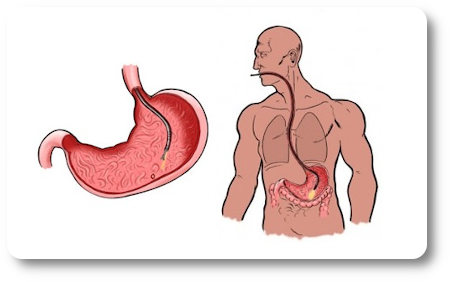

Информация и фотографии о хроническом гастрите и дуодените